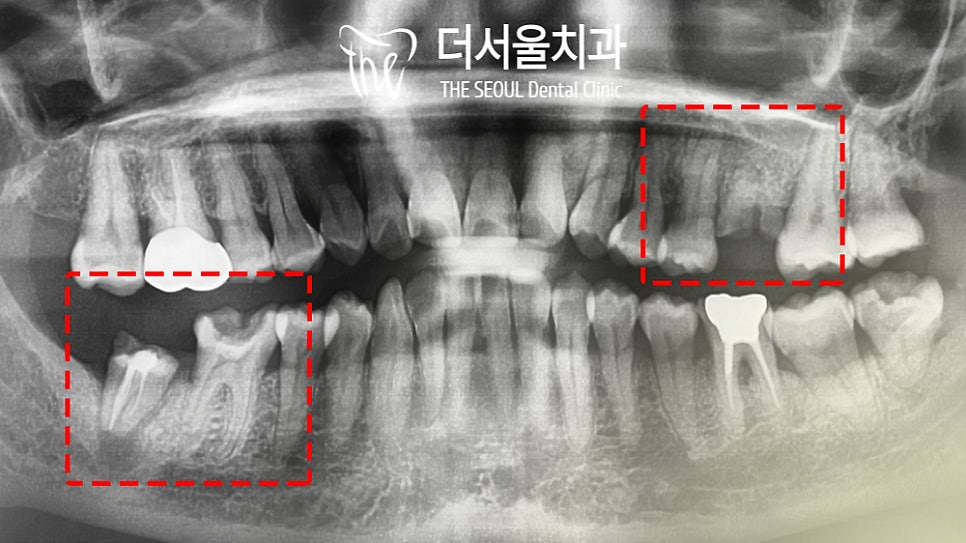

오랜 기간 진료를 받지 못했던 환자분,

그래서 그런지 여러 문제가 나타나 있었는데요.

뿌리만 남아 있는 곳들이 2곳이나 발견되었고

치아머리 부분이 크게 부러진 것도

추가로 확인할 수 있었습니다.